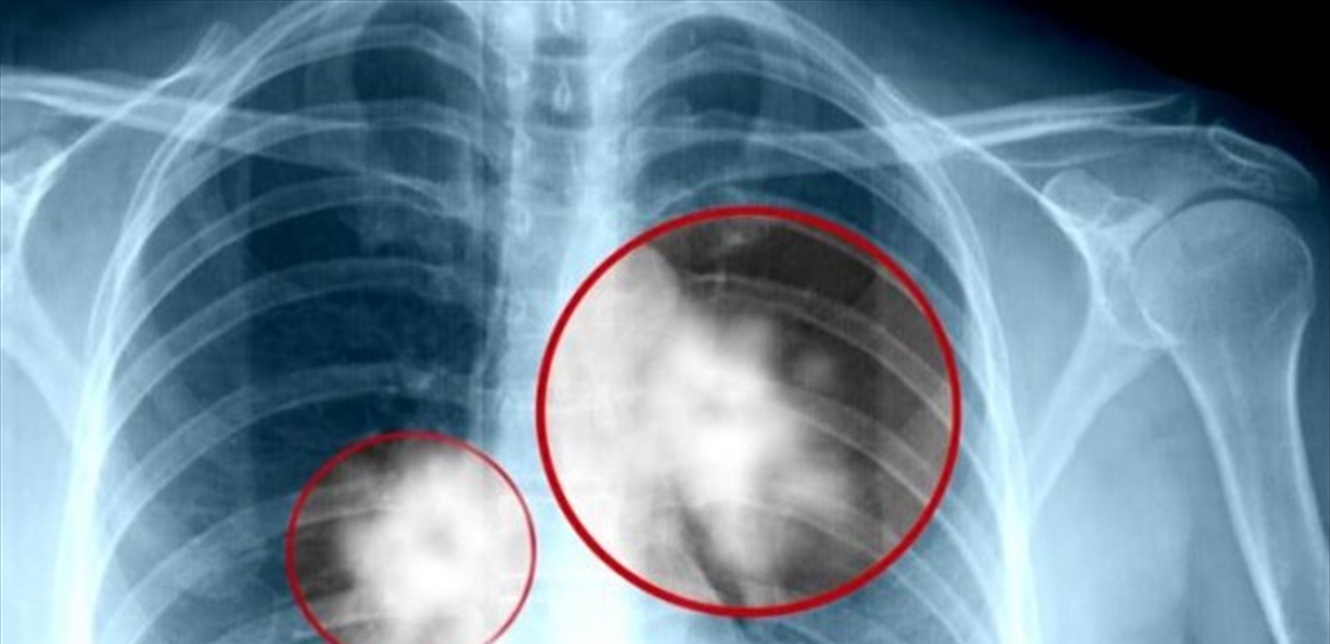

لا تتجاهلها.. 5 علامات رئيسية تشير إلى إصابتك بسرطان الرئة!

يعد سرطان الرئة ثاني أكثر أنواع السرطانات شيوعا في العالم، حيث يؤثر على الشعب الهوائية، وفي حالات نادرة، على الخلايا التي تبطن الحويصلات الرئوية، وفق تقرير لمجلة "آل" الفرنسية

وهناك عدة أنواع من سرطان الرئة، ولكن الأكثر شيوعا هو ما يسمى بسرطان الخلايا غير الصغيرة (NSCLC)، والذي يمثل ما يقرب من 85٪ من الحالات.

والرئتان خاليتان من الخلايا العصبية، مما يسمح للسرطان بالتطور دون أعراض مؤلمة لعدة أشهر، لكن هناك علامات يجب أن تحذر منها، سواء كنت مدخنا أمن لا.